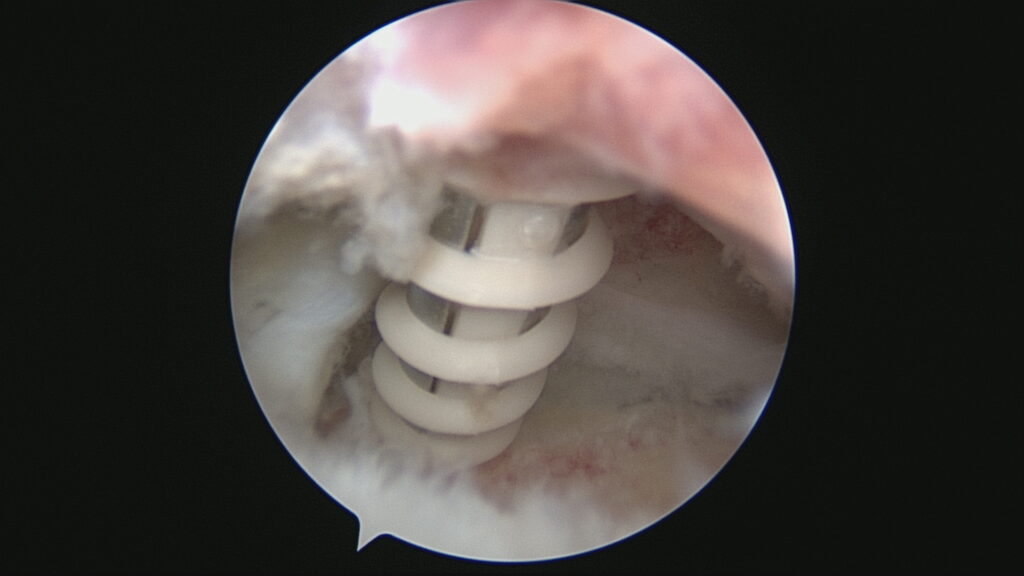

Lesión de Manguito Rotador

Reparación de Manguito Rotador con suturas y anclaje

Cirugía de reparación de manguito rotador con suturas y anclajes

Cirugía manguito rotador con suturas y anclajes